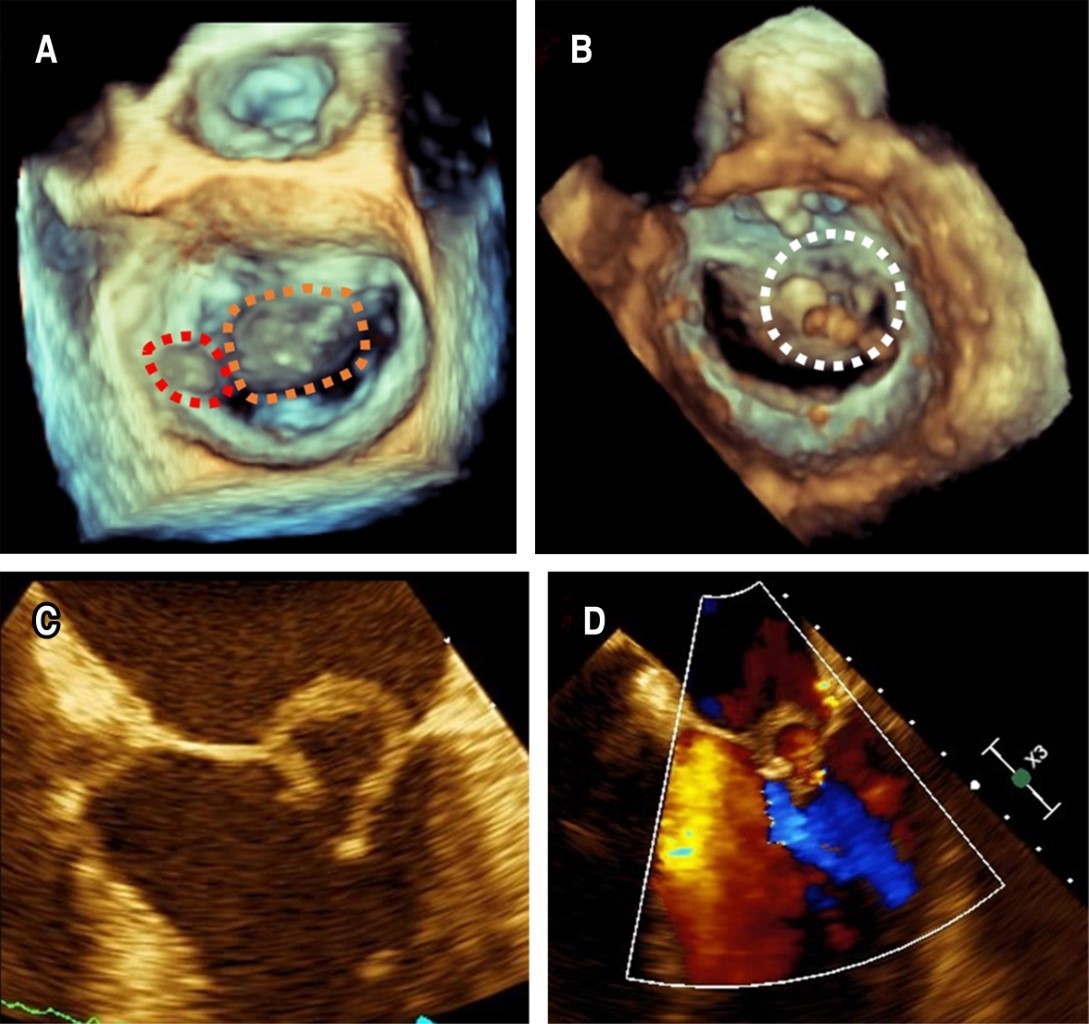

Based on the suspicion of IE, we obtained paired blood cultures and, subsequently, started vancomycin 1 g IV bid and ceftriaxone 1 g IV bid. A transesophageal echocardiogram (TEE) revealed an 11 × 5 mm vegetation on the P1 annulus of the mitral valve, a ruptured anterior mitral leaflet aneurysm resulting in severe mitral regurgitation accompanied by turbulent flow within the ruptured aneurysm (Figure 1) as well as a perforated non-coronary cusp of the aortic valve resulting in severe aortic regurgitation with regurgitation jet impinging on the anterior mitral leaflet (Figure 2). The blood cultures were positive for multi-sensitive Streptococcus gordonii, and antibiotics were deescalated to only ceftriaxone. Blood tests revealed a reduction in white blood cell count (8,400 mm3) and a decrease in inflammation markers (C-reactive protein 1 mg/dL, erythrocyte sedimentation rate 5 mm/h).

MVAs are extremely rare, usually associated with IE of the aortic valve, and the incidence is between 0.2 and 0.3% on echocardiography in general.6 There are several mechanisms of MVA formation: in the presence of aortic valve IE, the jet lesion may result in secondary destruction of the mitral valve due to: A) the jet damaging the endothelial surface of the mitral valve, B) retrograde dissemination of bacteria, or C) the presence of neovessels (prominent in AMVL) which results in localized inflammation, valvulitis, protrusion of weakened MV into the left atrium cavity, and subsequently aneurysmal formation.3,5,10 Respect retrograde dissemination might result from 1) direct contact between the aortic vegetation and the AMVL during diastole, known as "mitral kissing vegetations" when they exceed 6 mm in length, 2) secondary infection of the damaged endothelium by bacteria from regurgitation blood flow, or 3) local spread of the infection through the mitral-aortic intervalvular fibrosa.5

Approximately two-thirds of MVAs rupture or perforate; the size of the aneurysm does not correlate with the risk of perforation; the AMVL is much more commonly involved than the posterior leaflet for unknown reasons.5

The echocardiographic appearance of MVA is characterized by a saccular bulge of the mitral leaflets that extends into the left atrium during systole and collapses during diastole.5,11 Other echocardiographic features vary from small saccular bulges, often challenging to identify due to vegetation, to large leaflet protrusions towards the left atrium, which may be associated with various degrees of mitral regurgitation and thrombosis.12 Among the differential diagnoses of MVA are mitral valve diverticulum, blood cysts of the papillary muscle, cardiac masses, chordal rupture, non-bacterial thrombotic endocarditis, mitral valve prolapse, flailing mitral leaflets, myxomatous degeneration, and infective vegetations. The color flow Doppler can support a correct diagnosis. A high-velocity regurgitant jet and direct communication between the aneurysm and the left ventricle support the diagnosis of a perforated aneurysm.3,5

Figure 1